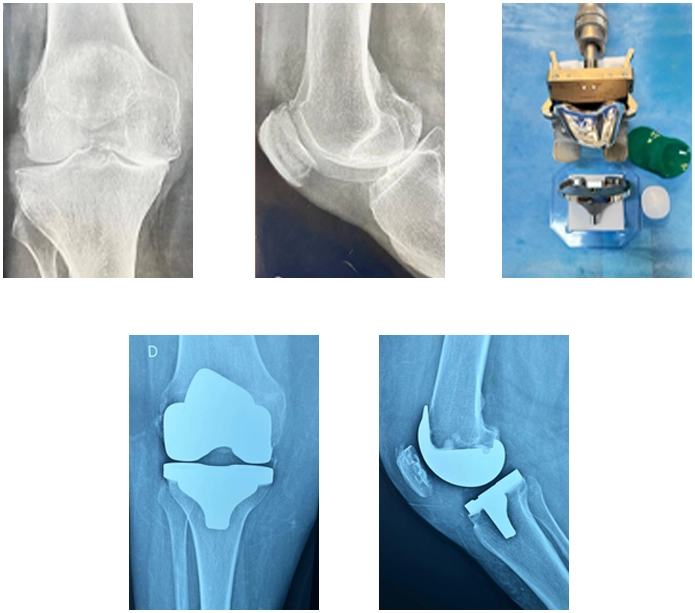

A artroplastia do joelho, também conhecida como substituição total do joelho, é um procedimento cirúrgico no qual a articulação do joelho é substituída por uma prótese artificial. É indicada para pacientes com artrose grave que não respondem ao tratamento conservador e apresentam dor e comprometimento funcional significativos. A artroplastia do joelho pode proporcionar alívio da dor e melhorar a mobilidade e qualidade de vida do paciente.